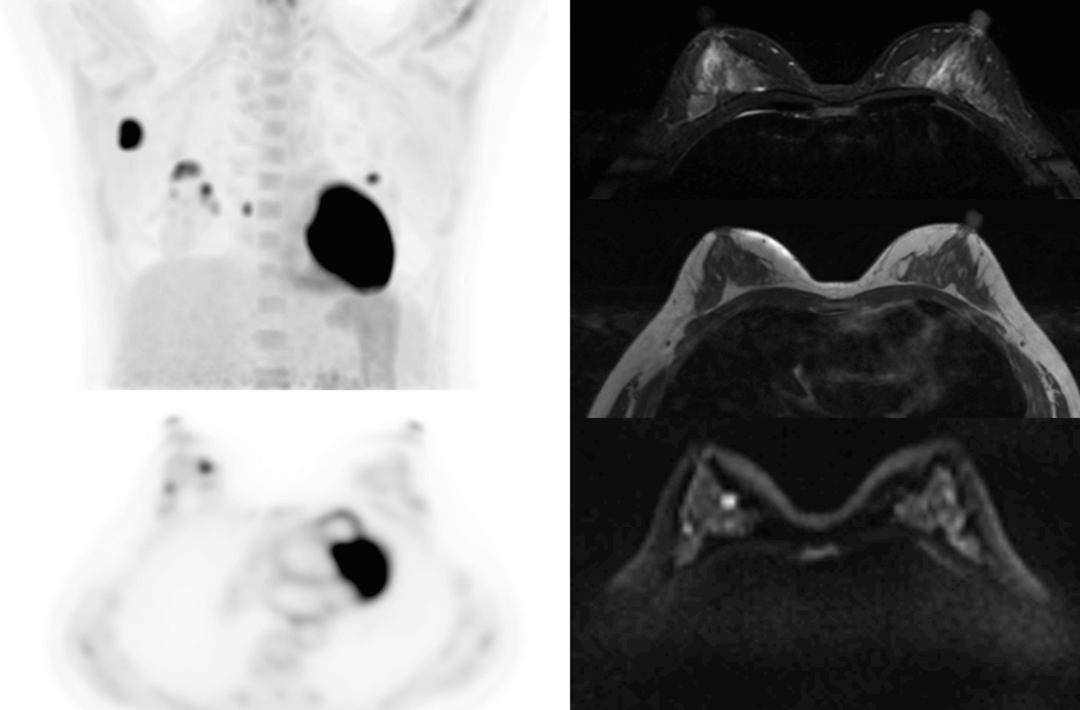

The following are the cases of optimized TNM staging of breast cancer, esophageal cancer, prostate cancer and other diseases under the long axial field of "spatio-temporal integration" ULTRA-clear TOF PET/MR. Thanks to Capital Medical University Xuanwu Medical Treatment for providing the image.